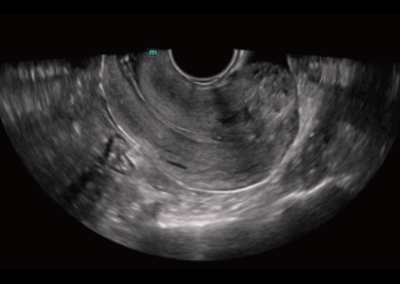

NueWa i9

El Nuewa I9, diseñado exclusivamente para mujeres y atención médica neonatal, brinda una experiencia innovadora integral. Estas innovaciones se desarrollan sobre la base de conocimientos profundos en escenarios clínicos complejos, para proporcionar respuestas precisas y oportunas, una gran eficiencia y una experiencia de usuario extraordinaria. •

- Diseño del panel de control inteligente y específico para exámenes clínicos con teclas especiales de tinta electrónica

- Diseño innovador con diseño adaptable para diferentes situaciones clínicas